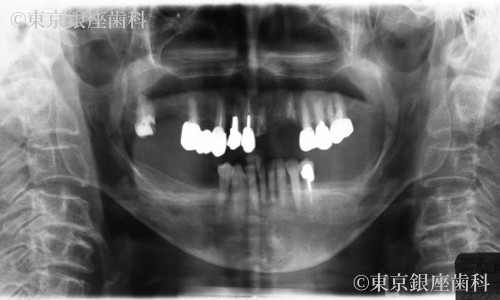

Before

全顎的な歯周病や虫歯、適合の良くないかぶせ物、不安定な噛み合わせ、不整な歯の並びであることを初診時に口腔内の診査とレントゲンにより診査し、咀嚼機能が低下していることが認められました。

上顎は予後不良(将来的に抜歯になる可能性が高い)な歯が多数認められ、また歯並びが不整であり咀嚼機能の低下、顎の運動が不自由になっておりました。